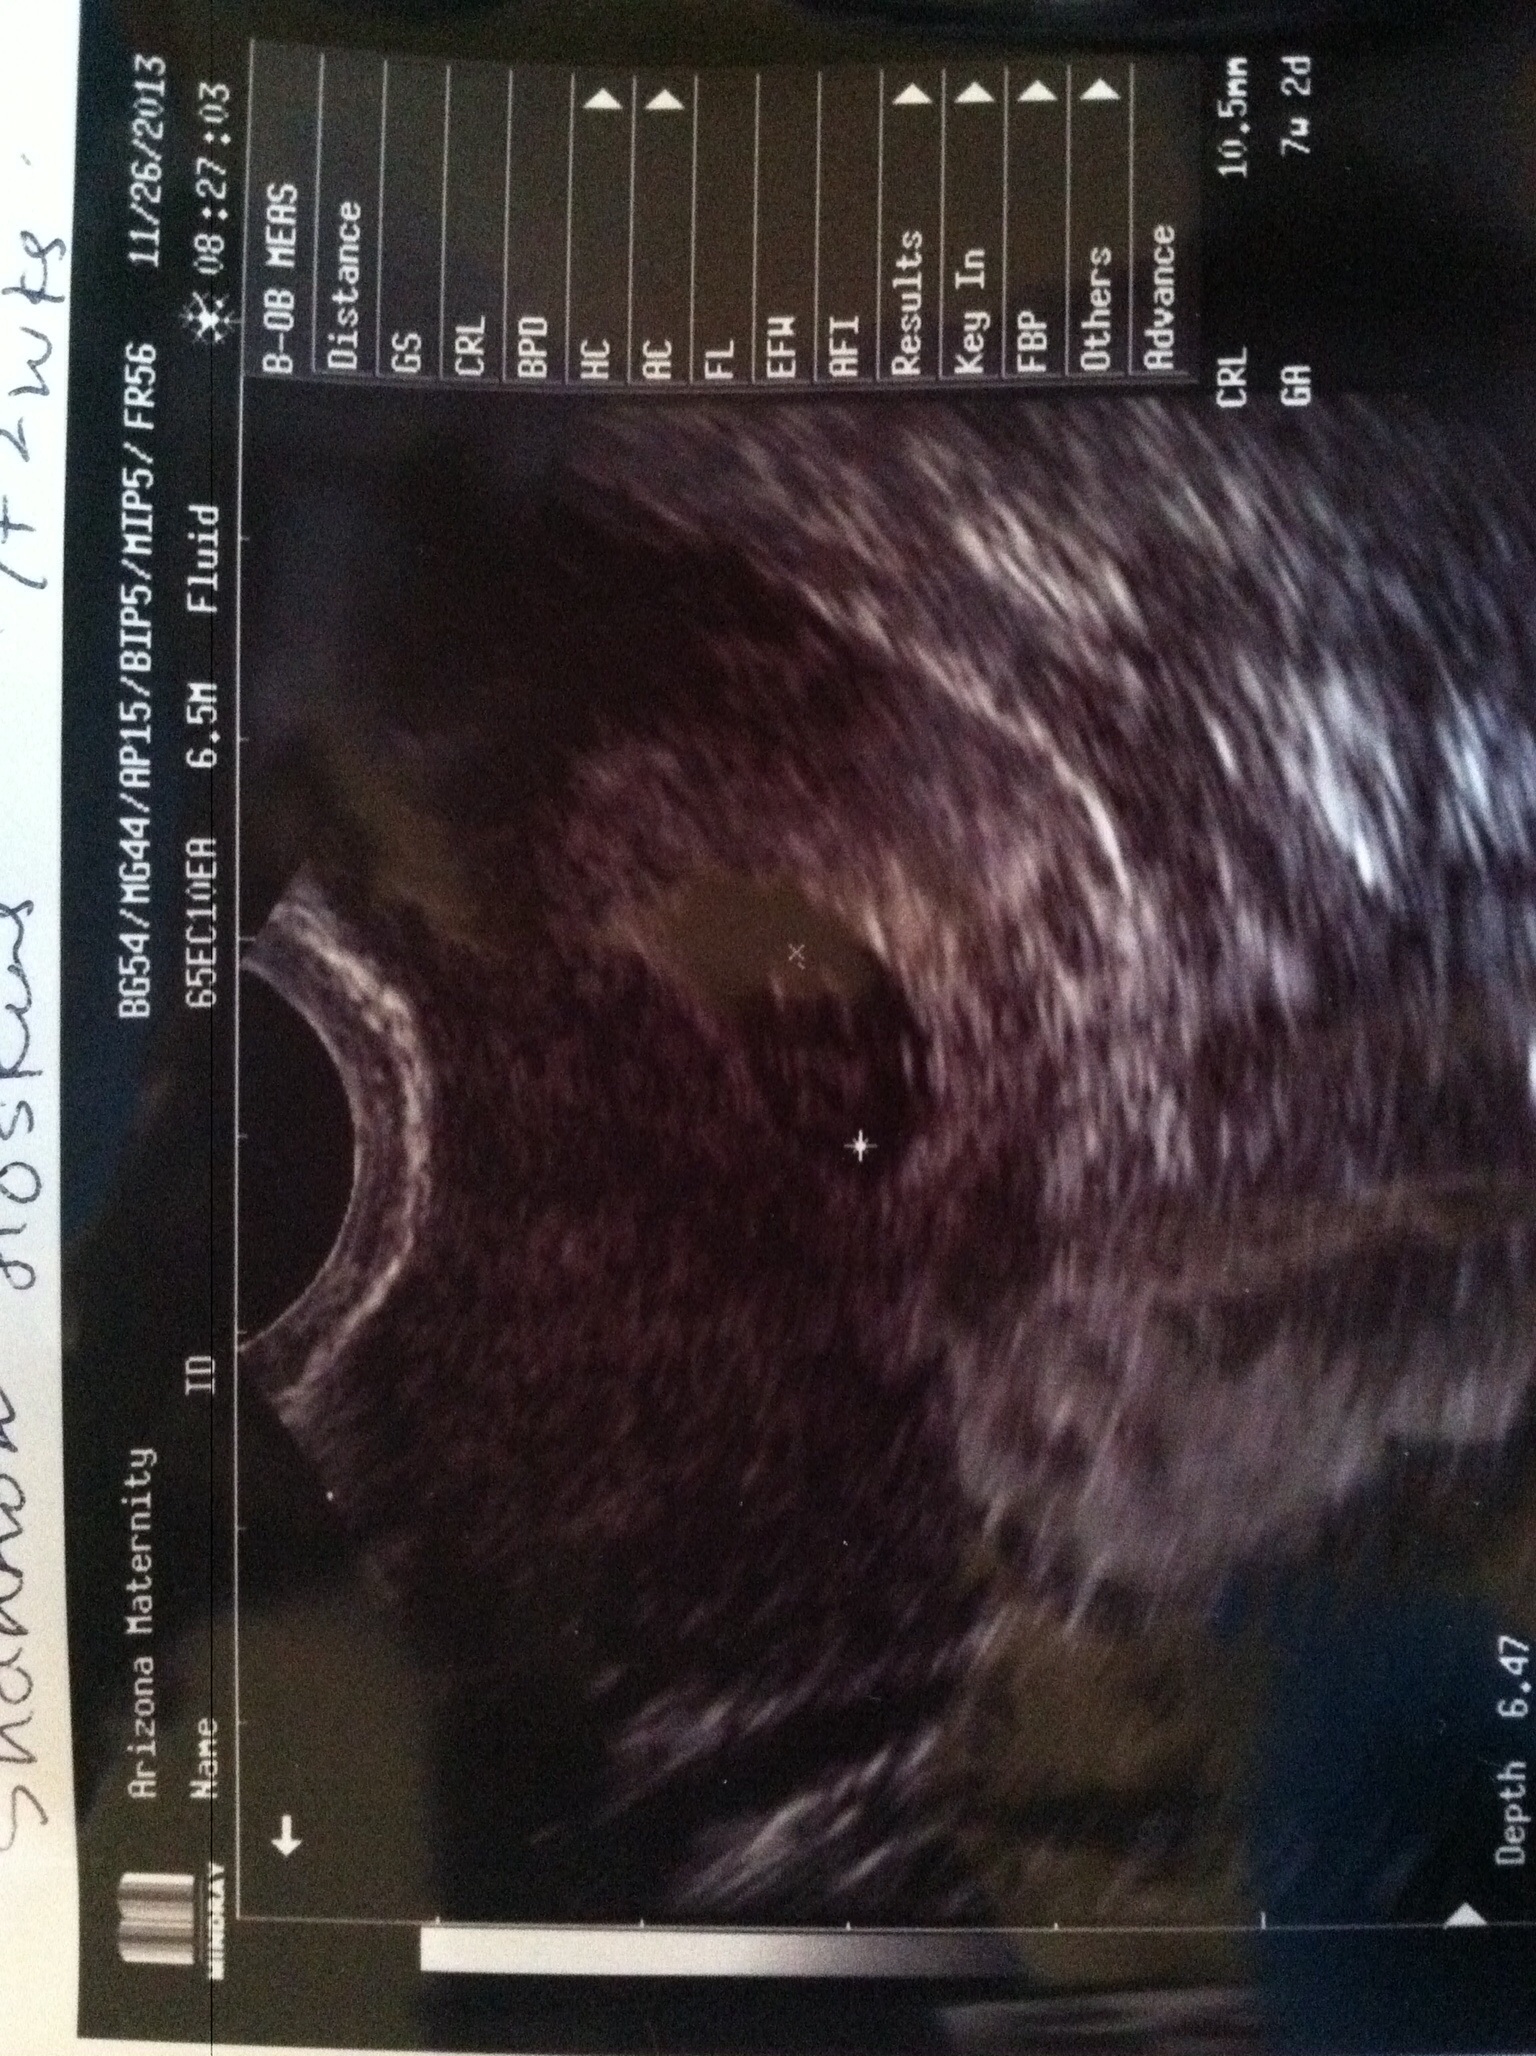

AW: 8wk u/s

We got to SEE the heartbeat! It was ridiculously cute! Like a fluttering. It was nice that DH could take a half day from work to go with me. We're going to announce to our parents right after thanksgiving. :-)

• I loved that u/s.  I was 7 weeks - it looked like a pixel flashing off and on!

• I loved seeing the heartbeat, it looked like a tiny butterfly. So glad you got to experience that today.

• Beautiful, it's an amazing sight.